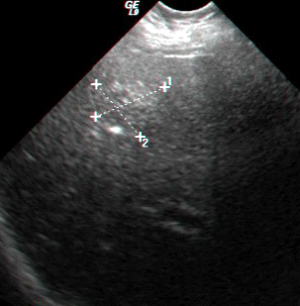

בבדיקות מעבדה: תפקודי הכבד לרוב תקינים, אך תיתכן עליה קלה ברמת האנזימים. האבחנה מתבצעת על ידי טומוגרפיה ממוחשבת (תמונה 26.10 ) או תהודה מגנטית (תמונה 27.10) כך שבדרך כלל אין צורך לקחת ביופסיה. באולטרה-סאונד ניתן להדגים גוש בכבד (תמונה 28.10).

| תמונה 28.10 : הדגמה של FNH באולטרה-סאונד כבד. השנתות מצביעות על גודל השאת. |